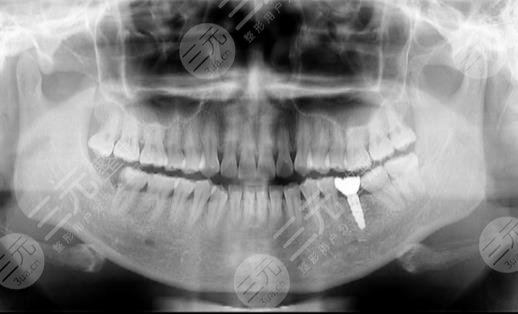

我有一颗牙齿掉了,平时吃饭较为的不舒服,所以我就想要去种植牙齿,开始的时候我还以为没有办法种植,因为是后牙,这样对我的影响特别大,对于我的饮食有很大的影响,但在种植牙齿的时候又不知道选择哪家医院,后来了解之后才知道广州穗华口腔医院的经验特别的丰富,而且对于种植牙齿的时候可以就个人的情况详细的进行分析。

在种植牙齿的时候,医生给我制定了一套较为不错的案例,然后根据我的情况适当的分析了一番,后来选择了材质比较好的牙齿,虽然价格相对贵一些,但是比我想象的还要便宜呢。在开始种植牙齿的时候还是有点紧张,首先要把口腔进行清洁,然后需要把牙齿打磨之后然后制作出来。

整个的过程大概需要20天左右才完成的,这个过程对于我来说还是挺漫长的,如果在种植牙齿的时候,刚开始我总是感觉吃东西不是特别的得劲,总是感觉吃东西的时候牙齿特别的不舒服,没有任何的力气,但是过了一段时间之后好多了。现在用这把牙齿已经有一个多月的时间和牙齿的颜色没有任何的亮一样,比我想象中的还要漂亮,所以我较为感谢这里的医生。